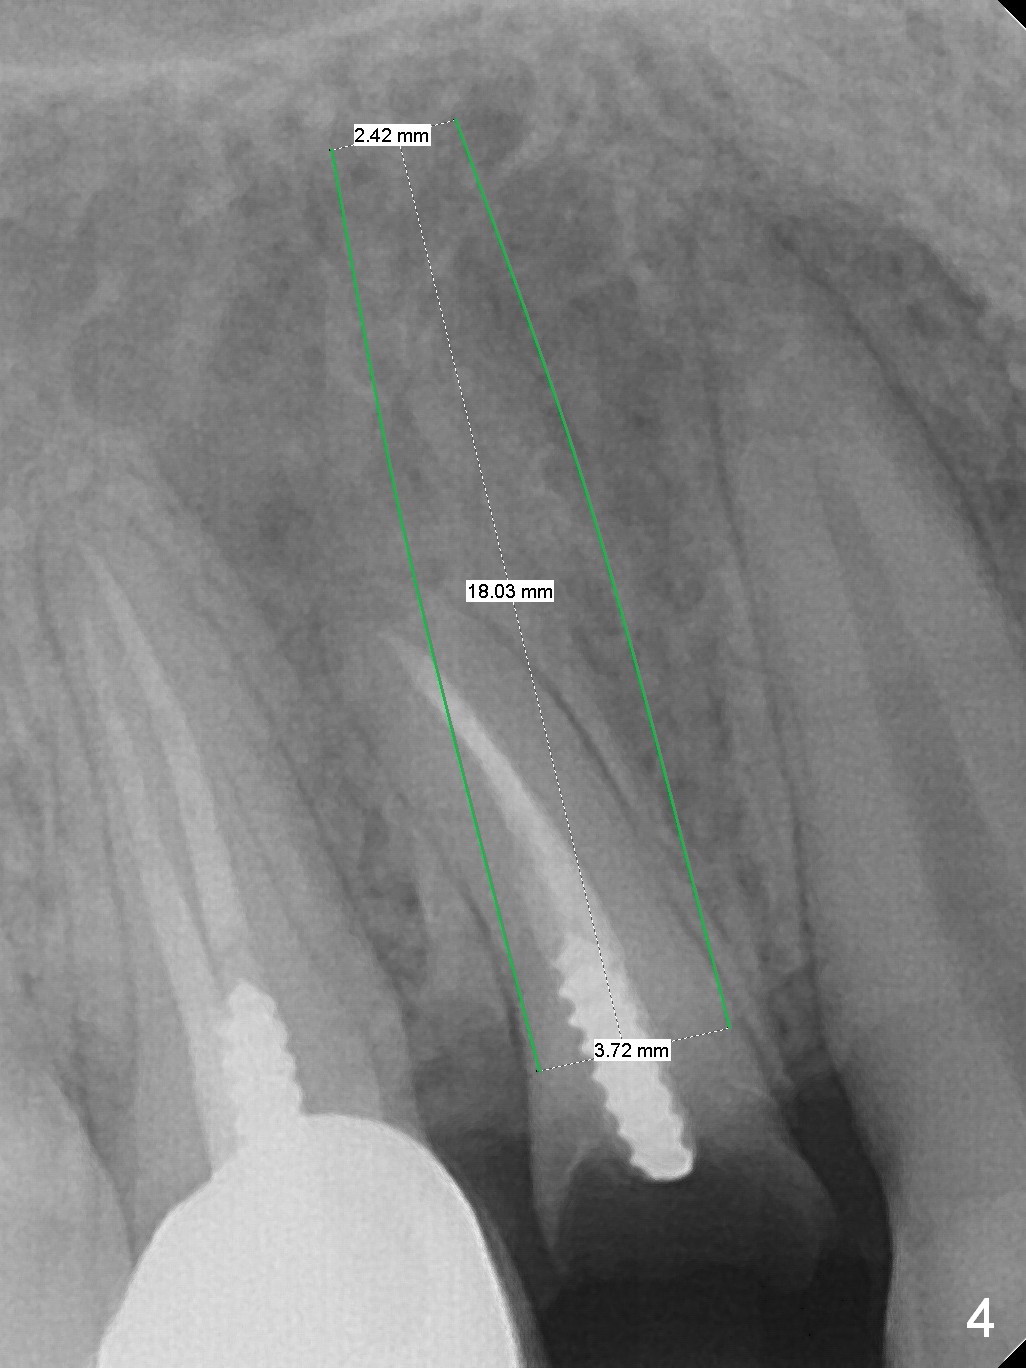

A 34-year-old man (smoker, half a pack a day) has residual root at #5 (Fig.1) with large periapical radiolucency (Fig.2 red dashed line). Since the root curves distally (Fig.3 black area, Clindamycin), osteotomy will be established in the mesial wall (red long arrow). A 3.8x16 or 18 mm implant is to be placed for primary stability (Fig.4). To reduce periimplantitis associated with smoking, place the implant deep. The implant appears to have better surface treatment. Pack sufficient bone graft and membrane. Immediate provisional should have good seal. To place the implant deep, osteotomy will be attempted with a long 1.5 mm pilot drill (PA), followed by 2 mm one with extension and 3.0x18 mm drill.